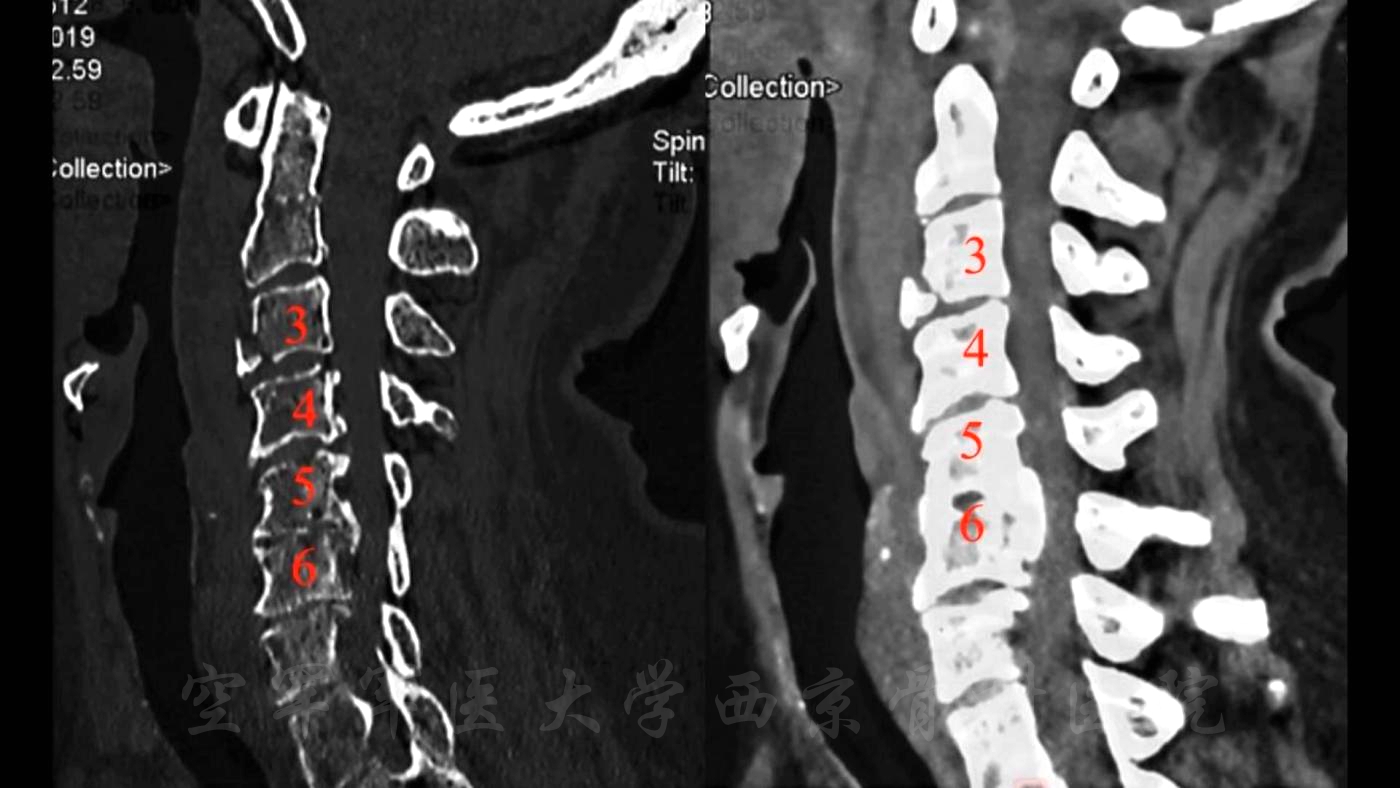

颈椎后路椎板切除减压,C3-6侧块螺钉、C2椎弓根螺钉固定,植骨融合手术

术前CT